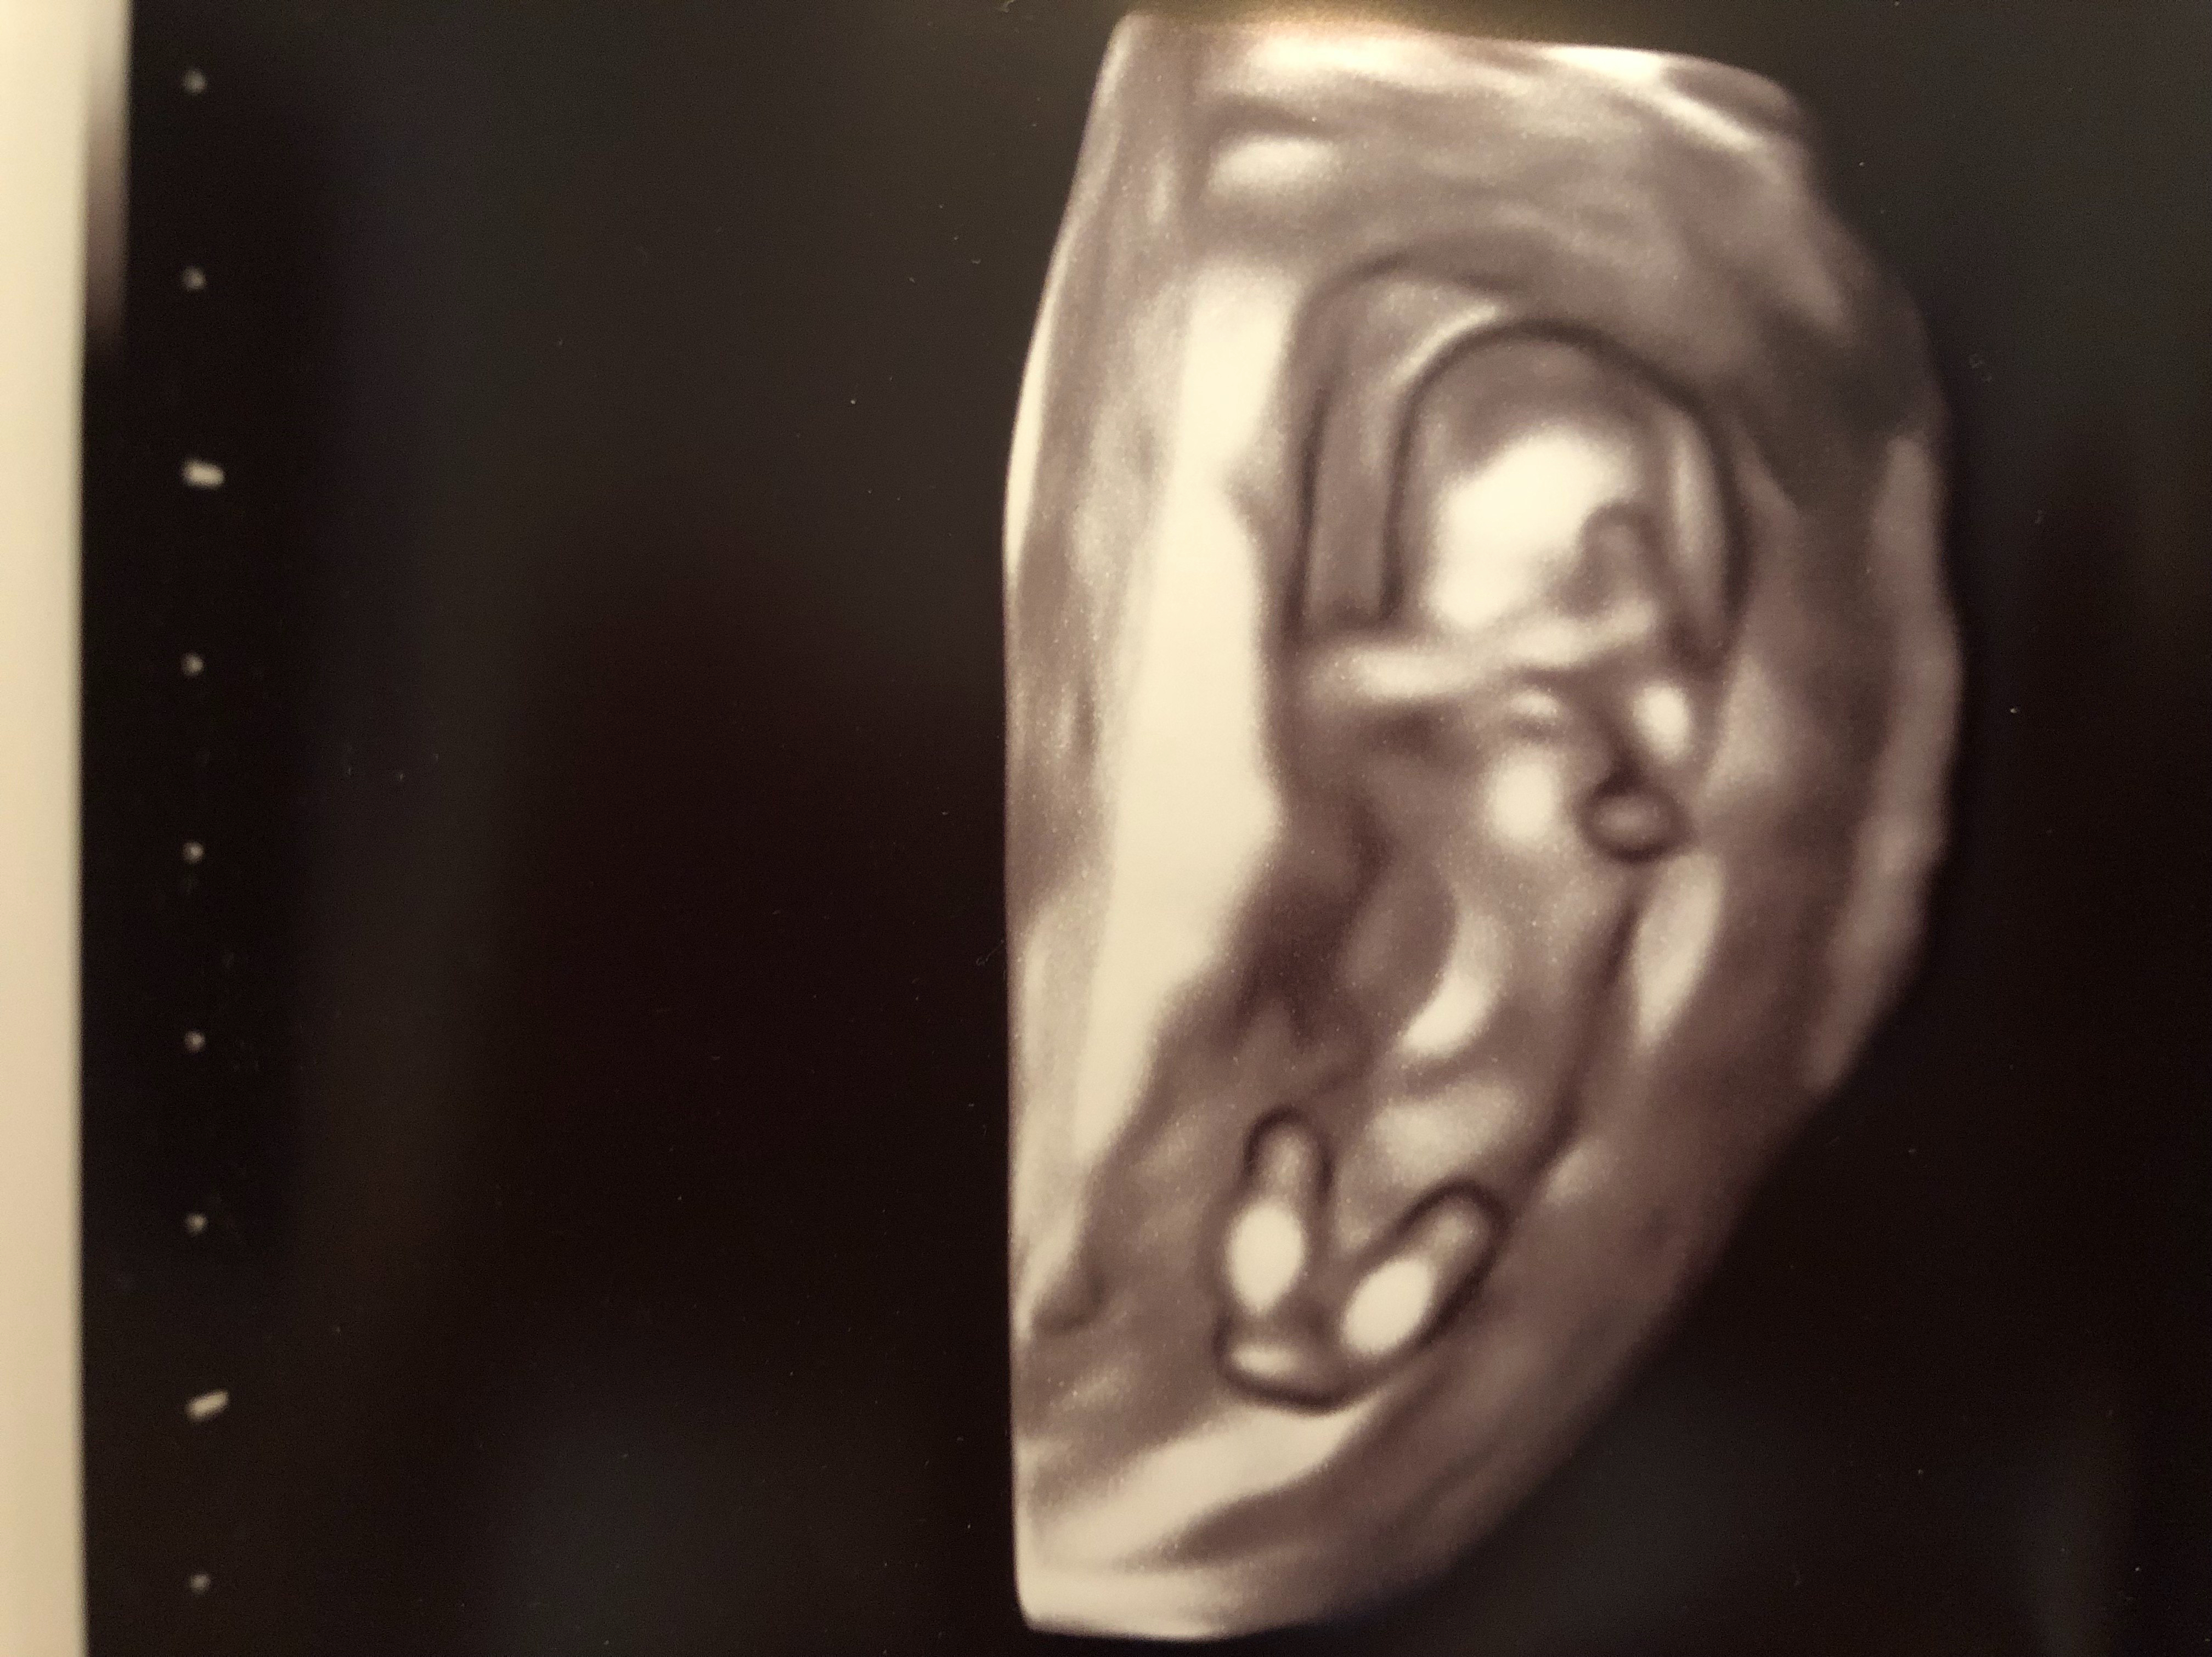

IMG_0920 Share this:Tweet Email a link to a friend (Opens in new window) Email Print (Opens in new window) Print Like Loading... Published by teamwac View all posts by teamwac